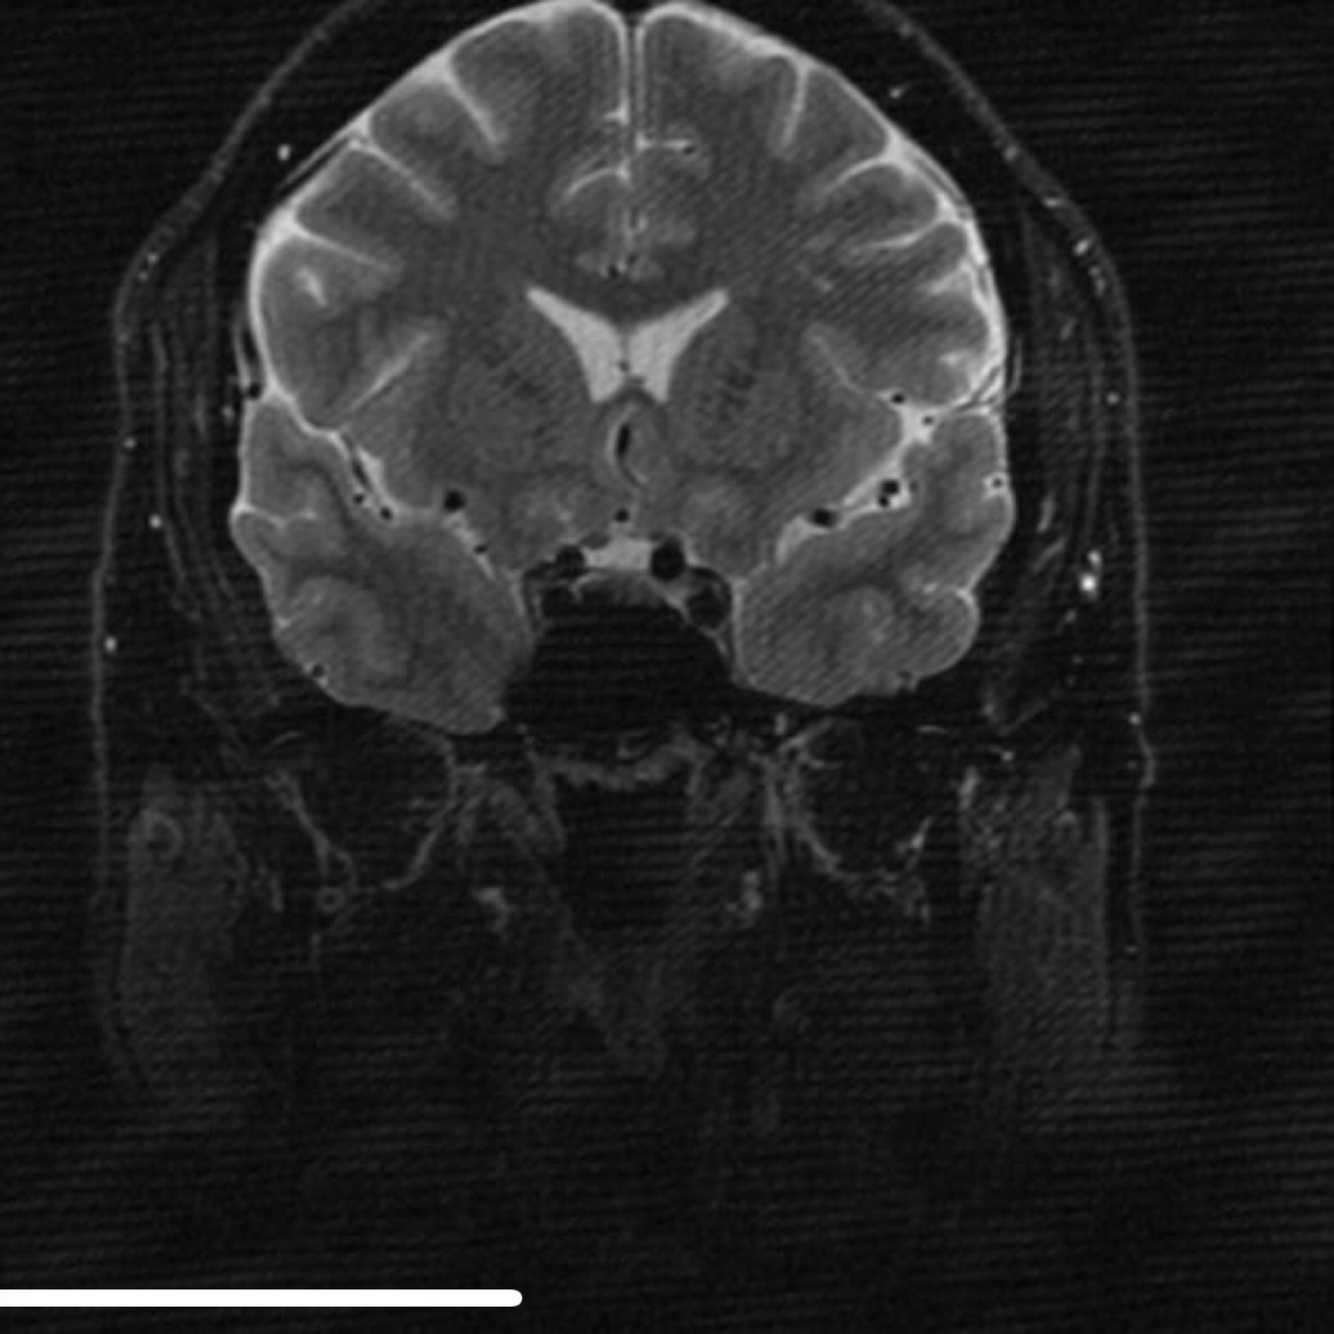

Aliasing on MRI, also known as wrap-around, is a frequently encountered MRI artifact that occurs when the field of view (FOV) is smaller than the body part being imaged. The part of the body that lies beyond the edge of the FOV is projected onto the other side of the image. This can be corrected, if necessary, by oversampling the data. In the frequency direction, this is accomplished by sampling the signal twice as fast. In the phase direction, the number of phase-encoding steps must be increased with a longer study as a result. However, if the FOV and matrix size (phase-encoding steps) are increased and simultaneously number of excitations (or number of signal averages) reduced to half, the imaging time can be kept constant with correction of aliasing. Case 1 demonstrates axial T2-weighted images of the brain that demonstrates aliasing. The first image shows wrap-around with the back of the head projected over the front because the phase-encoded direction is anterior-posterior and the FOV is too small.

Fix: phase and frequency directions reversal resulting in absence of the aliasing artifact. Oversampling is used in the phase direction to eliminate the aliasing.